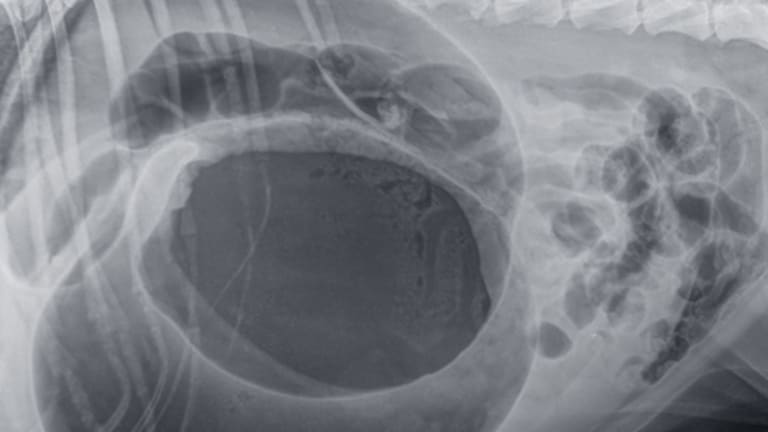

csomorcsavar röntgenkép

kép: gyomorcsavarodás kutyáknál